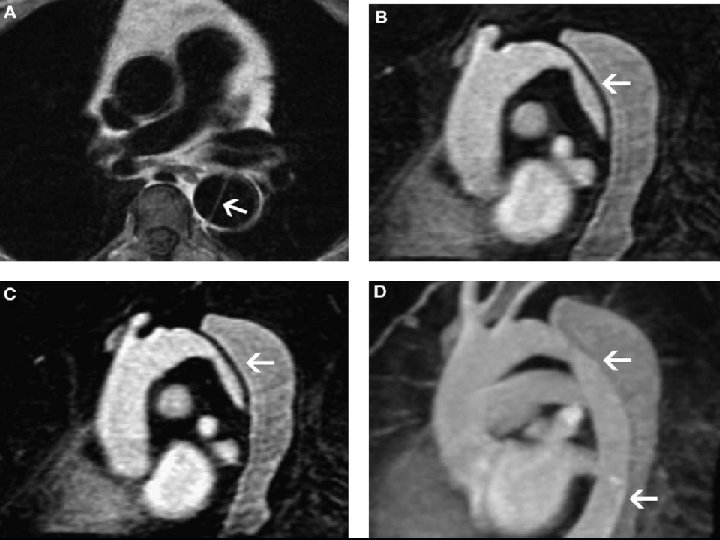

53 -18 y 53 -19

LABORATORIO RM • Sensibilidad y especificidad del 98% • Angiograma con gadolinio • Ventajas • No invasivo • No medio de contraste ionizante • Múltiples cortes

LABORATORIO RM • Desventajas • Disponibilidad • Pacientes con marcapasos, clips • No consistente identificación de IM • Problemas para monitoreo y tratamiento • Seguimiento posquirúrgico • Evaluación de lesiones crónicas